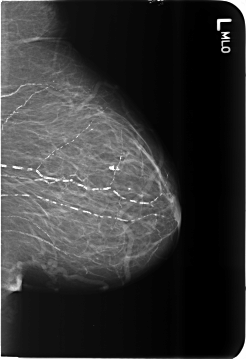

B_3481_1.LEFT_MLO

LEFT_MLO LINES 5736 PIXELS_PER_LINE 3936 BITS_PER_PIXEL 12 RESOLUTION 50 NON_OVERLAY